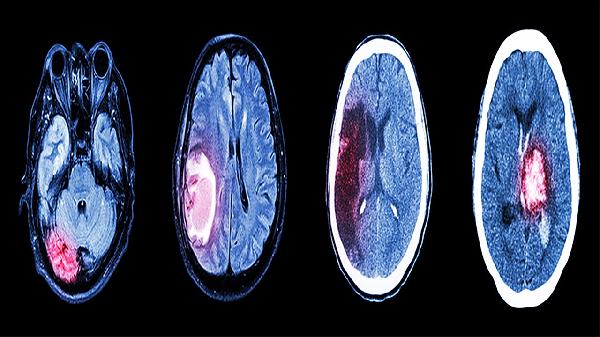

脑膜炎或颅内占位可能导致颅压增高,引发枕部搏动性疼痛伴喷射性呕吐。需通过头颅CT排查,若确诊为细菌性脑膜炎需静脉注射注射用头孢曲松钠,肿瘤患者则需根据病理类型制定放化疗方案。任何伴随意识障碍的情况均需急诊处理。